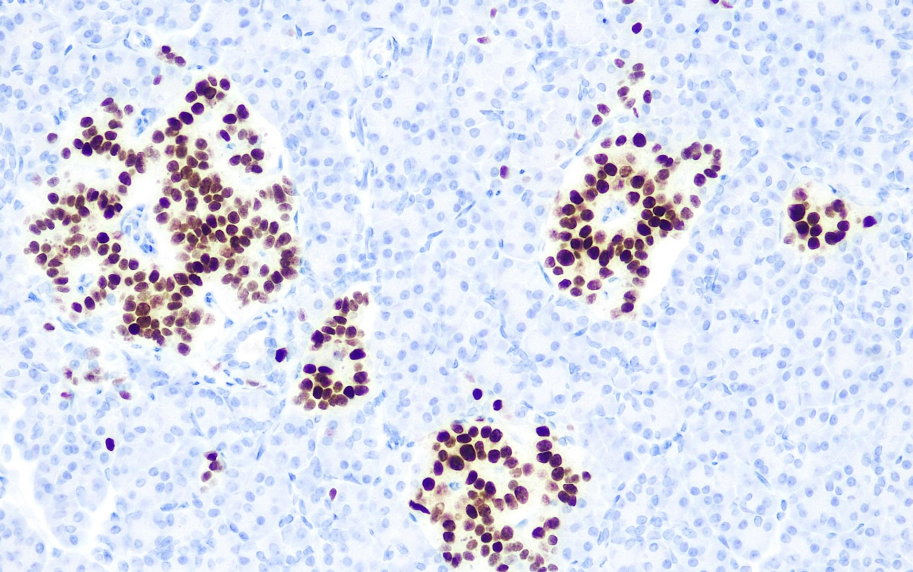

Cellular localization: nucleus

Positive control: Pancreas

The INSM-1 gene is located on chromosome 20p11 and is also known as KLF16. It was first reported in 1992 and is a zinc finger protein with DNA-binding transcriptional regulatory functions. It plays a significant role in neurogenesis and neuroendocrine differentiation and can serve as a broad-spectrum neuroendocrine marker. The sensitivity is comparable to Synaptophysin and CD56, and superior to Chromogranin A.

The INSM-1 antibody reagent can specifically bind to the INSM-1 molecular antigen. The immunohistochemical kit containing the INSM-1 antibody reagent is suitable for the precise diagnosis of carcinoid, lung, head and neck endocrine tumors, primary central nervous system tumors, small cell carcinoma and Merkel cell carcinoma originating from the prostate and cervix.